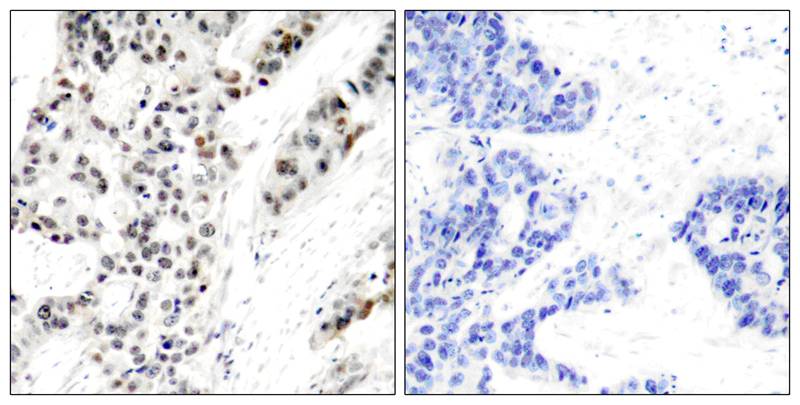

分类: 科研抗体货号: P40092别名: Tumor suppressor p53; Phosphoprotein p53; Antigen NY-CO-13; TP53;应用: WB,IHC,IF反应种属: Human